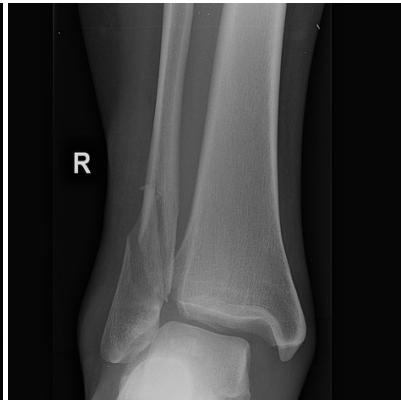

Reading an X-Ray of Ankle Joint Injury

Key Measurements

Tibiofibular Clear Space

- Normal: < 6 mm (AP view)

- Pathological: ≥ 6 mm

Tibiofibular Overlap

- Normal: ≥ 6 mm (AP view)

- Normal: ≥ 2.8 mm (mortise view)

Medial Clear Space

- Normal: < 4-5 mm (mortise view)